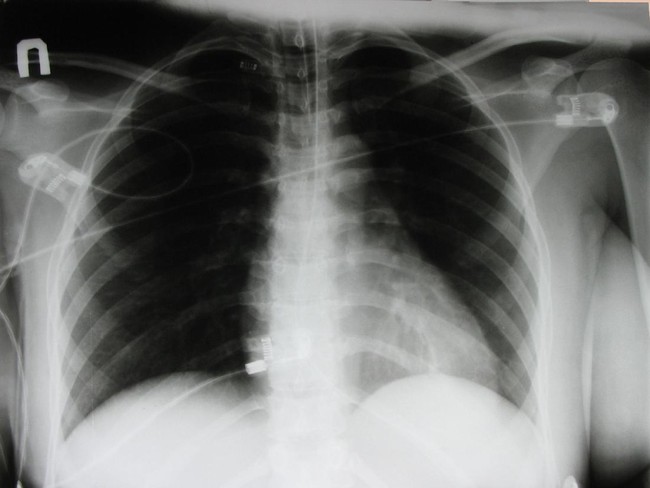

Ada berbagai hal yang bisa memicu kanker paru. (Foto ilustrasi: thinkstock)